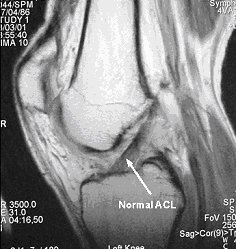

This will show all the structures in the knee and enables a reliable diagnosis to be made however, scans are very expensive and are not always available or if they are, there may be an unacceptably long wait.

A. The first image demonstrates an intact cruciate ligament.